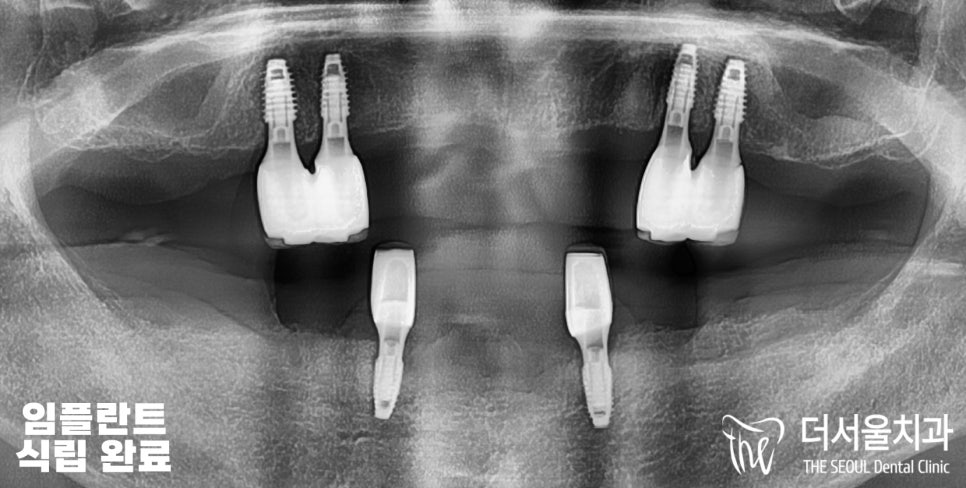

태평동치과 에서 치료 결과를

전,중,후 3단계로 나눠서

보여드리고 있습니다.

확실히 치료가 끝나고 나니

처음 상태보다 나아진 것을 볼 수 있습니다.

환자분 또한 보험 혜택 적용을 받은 것과

최종 결과가 너무 마음에 든다며,

윗니 아랫니가 서로 부딪히는 게

얼마만이냐며 정말 좋다고 말씀해 주셨습니다.